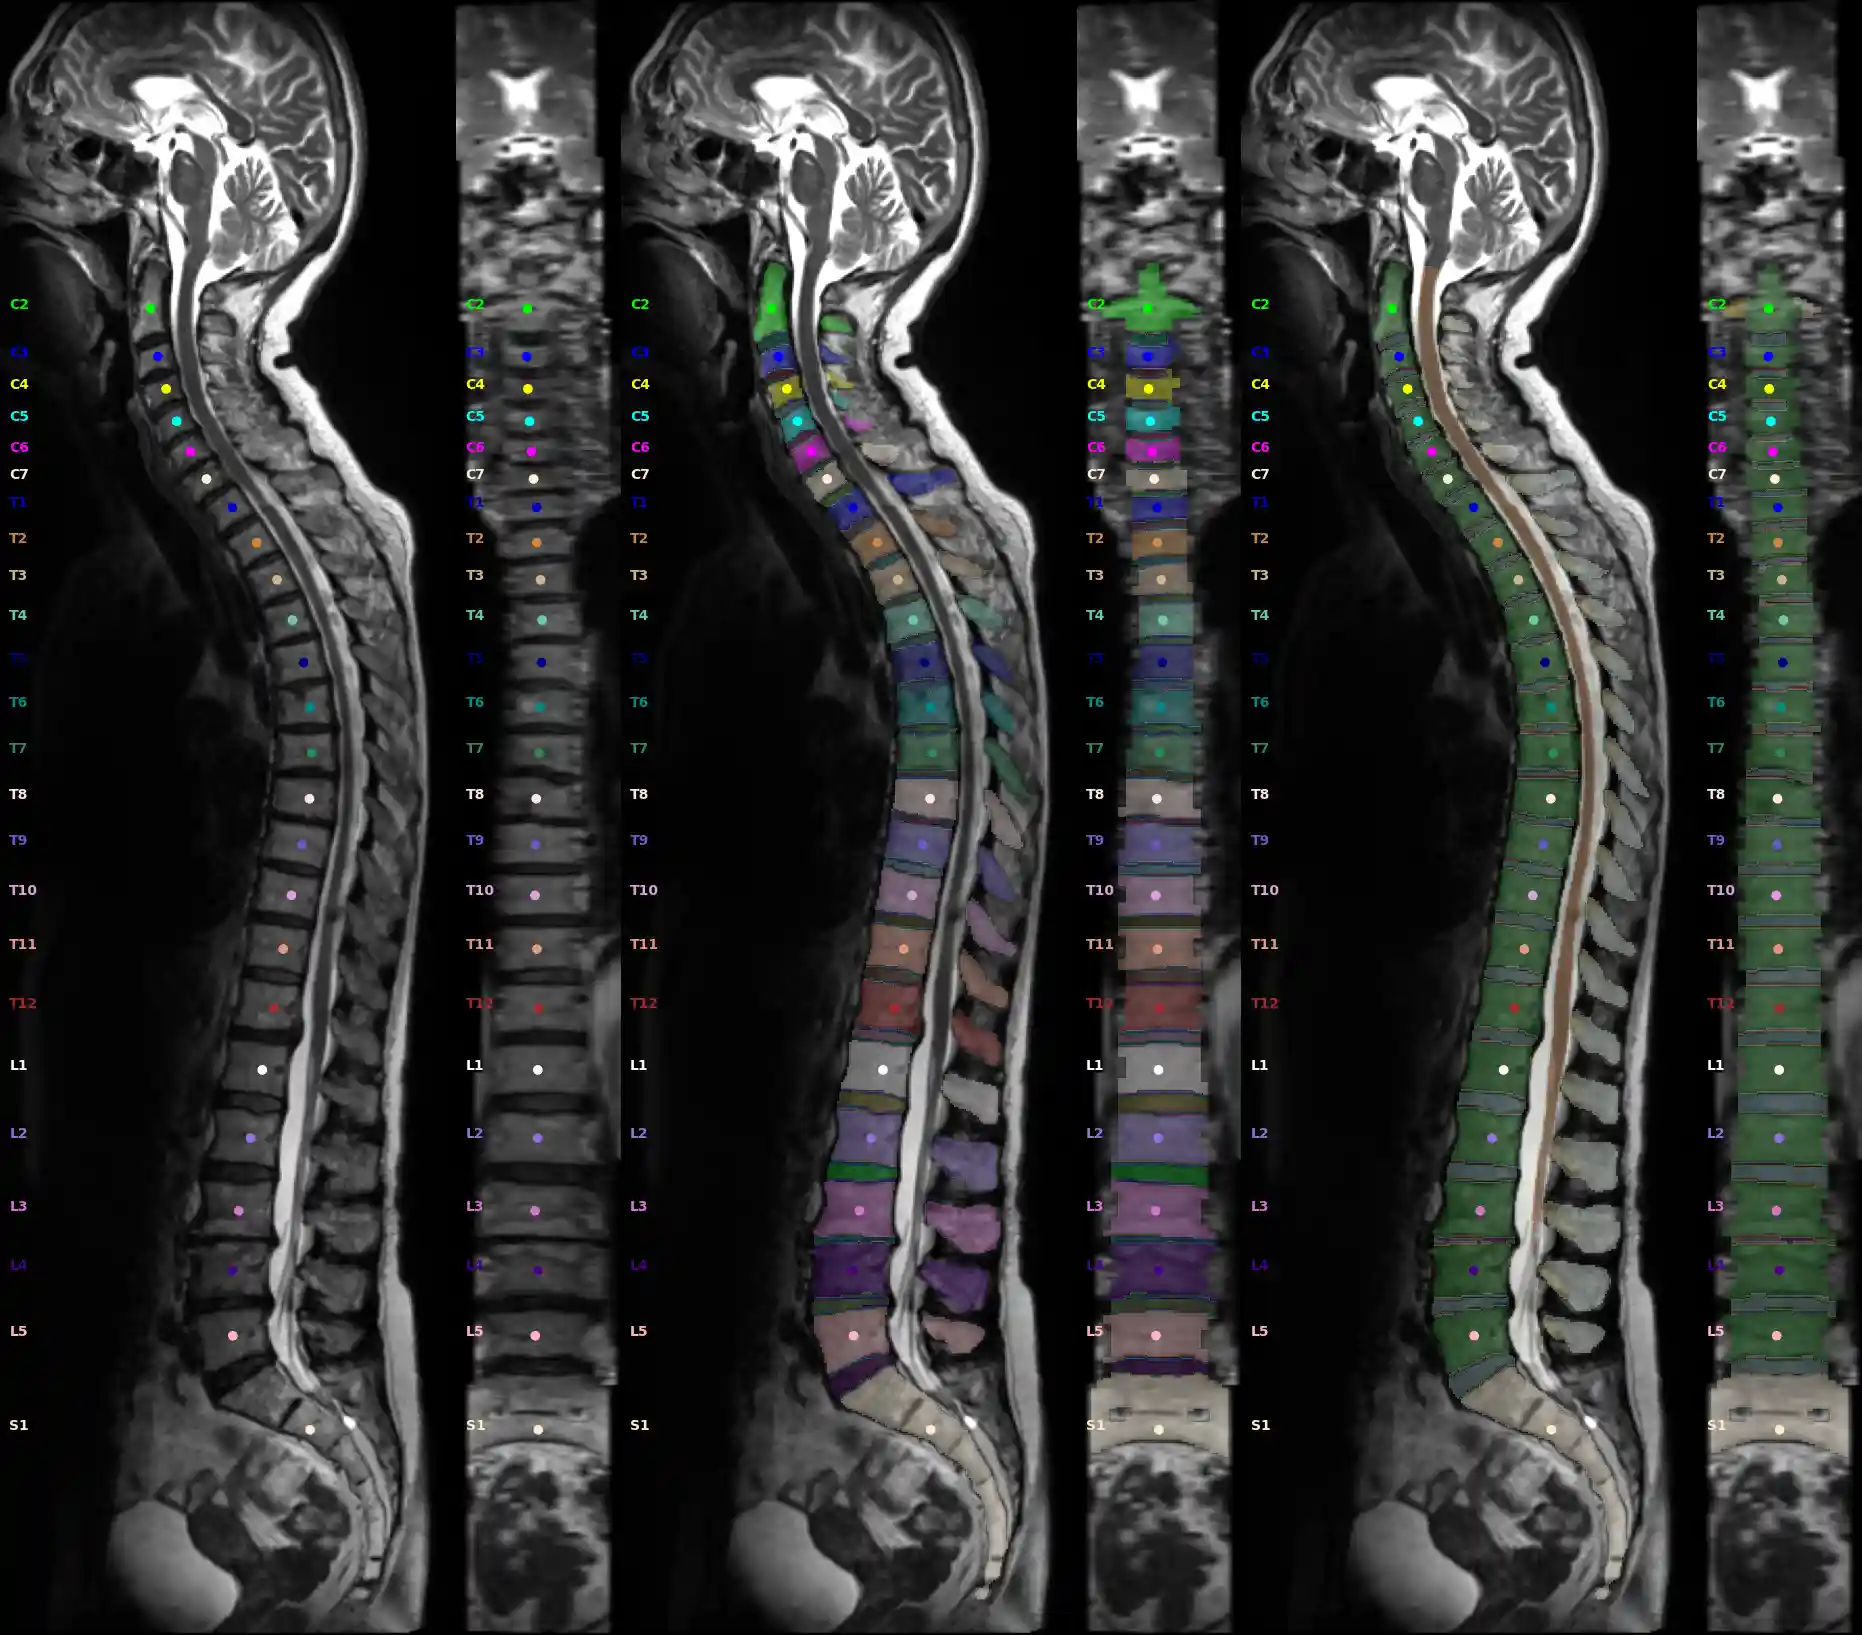

Spineps and Points of Interests (POI) integration

For our Spine segmentation pipline follow the installation of SPINEPS.

Image Source: Rule-based Key-Point Extraction for MR-Guided Biomechanical Digital Twins of the Spine;

SPINEPS will produce two mask: instance and semantic labels. With these we can compute our POIs. There are either center of mass points or surface points with bioloical meaning. See Validation of a Patient-Specific Musculoskeletal Model for Lumbar Load Estimation Generated by an Automated Pipeline From Whole Body CT